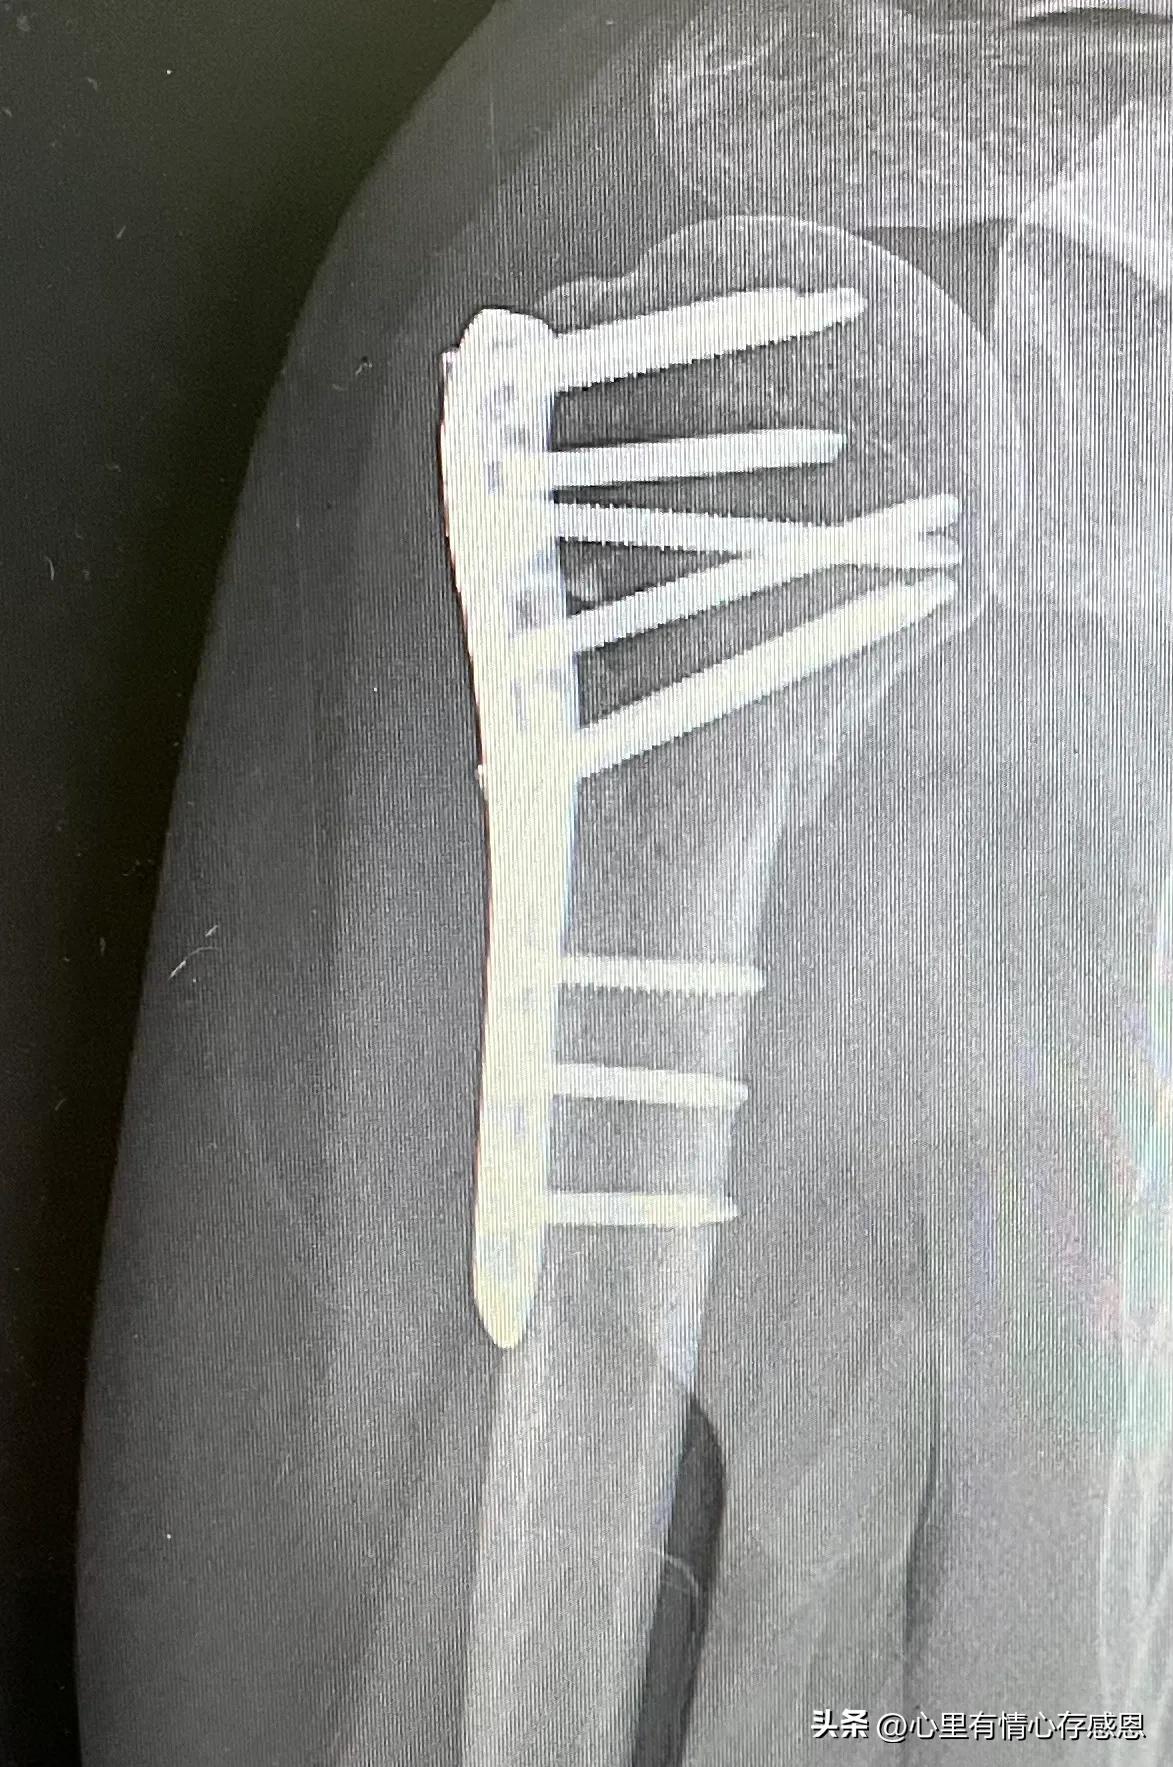

我的右手臂肱骨骨折术后已经整整四个月了,昨天又去医院复诊,康复医生又教了我三个新的训练方法,让我每天练习6到10次。

第三个月复诊时,让我做四个动作(躺下被动抬手过头、坐位背后拉手过左髋、双手爬墙、双手抱头肘部外展),经医生评估,我一个动作都没做到位,主要我太怕痛了。